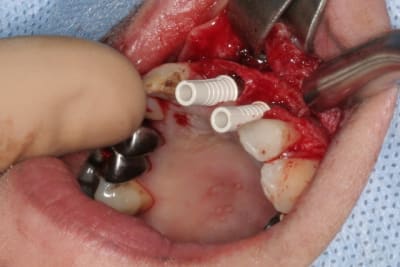

cet implant est une merveille!!!

connexion au top, pièces prothétiques aussi, facilité de pose incroyable...

tien, ce matin, extraction de 24/25, curetage méticuleux, forage, comblement du gap, pose des 2 implants qui se sont bloqués à 50Ncm au CA sur les 3 ou 4 mm apicaux, pose des vis de cicat, sutures...35min....tranquille...

désolé, la pano est un poil déformée (la patiente à du bouger...)